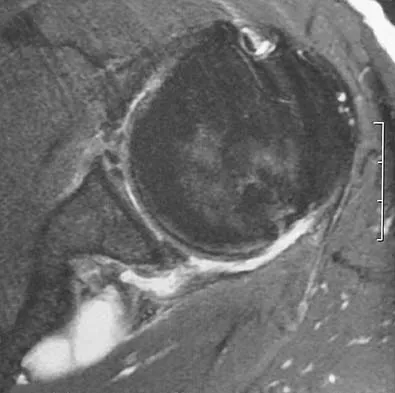

Question 88

Figure 41 shows the MRI scan of a 39-year-old man who has severe left groin and anterior thigh pain. What is the most likely diagnosis?

Explanation